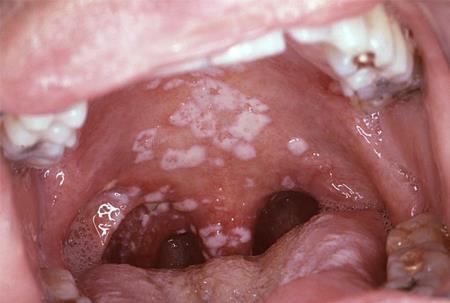

Searching for "oral infections ulcers"